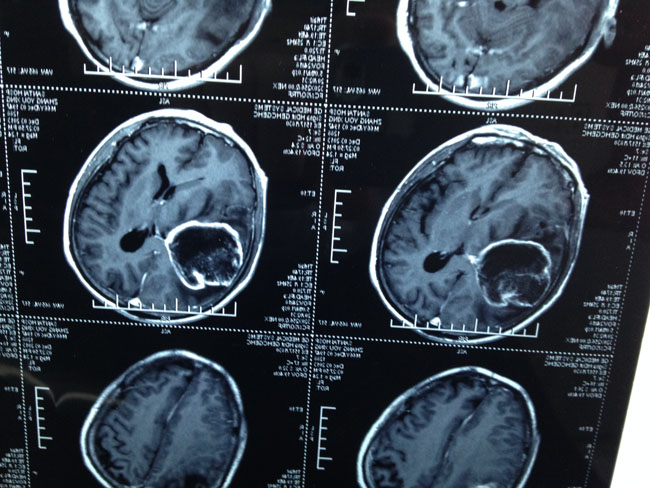

到了神经外科病房,今天安排的手术病人已经送到手术室了,(脑胶质瘤),病房的另一位脑外伤后遗症3个月还没有醒。检查了病人后,目前主要是肺部并发症。需要营养支持,抗感染治疗,高压氧治疗等等综合措施。9:30分左右到手术室,在当地的医生的配合下,用了2个半小时将胶质瘤全部切除。手术非常顺利。12:00结束。午饭是当地医院神经外科主任招待的。饭后13:30医院安排送我去了机场,乘15:20分飞机16:30到了上海虹桥机场。1天时间往返1160公里。手术又顺利。这个就是白衣天使的一天。爱心+责任心+高超的技术=白衣天使。

4.脑胶质瘤病人.JPG

3.脑胶质瘤病人 (1).JPG